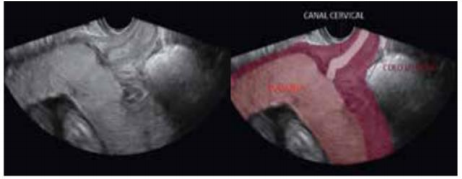

O sangramento vaginal que ocorre durante o terceiro trimestre de gravidez, é motivo de preocupação, tanto para a paciente quanto para o obstetra. Dentre todos os episódios de hemorragia do terceiro trimestre, aproximadamente 20% são devidos à placenta prévia. A placenta prévia vem se tornando cada vez mais frequente, paralelamente ao crescente índice de cesarianas, um dos seus principais fatores predisponentes. Quando a placentação ocorre no segmento inferior do útero, de forma que fique abaixo da apresentação fetal e recubra o orifício interno do colo uterino parcial ou completamente, após o período de migração placentária, está presente a placenta prévia. A adequada classificação da placenta prévia é de suma importância, uma vez que sua avaliação está relacionada com o sucesso da gestação, sendo assim, assinale a imagem de US abaixo e faça a correta classificação: